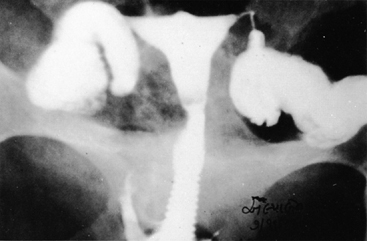

No characteristic radiographic features are pathognomonic for genital tract TB, although certain findings should raise suspicion of its possibility. Barter and associates reported that an abdominal film may show calcified pelvic and abdominal lymph nodes, a characteristic and recognized sequela of healed genital tract TBs.83 Hysterosalpingography may reveal certain abnormalities that suggest the possibility of pelvic TB. The uterine cavity is classically shriveled and deformed, with associated intrauterine adhesions and lymphatic extravasation (Fig. 6). The fallopian tubes often show ragged outlines with multiple strictures, giving a beaded appearance (Fig. 7); in some patients, the entire tube appears rigid and may exhibit small terminal sacculations of the ampullary end (Fig. 8). Fistulous tracts between the genital tract and other pelvic organs may be identified. Occlusion of the digital end of the fallopian tubes is common, although marked hydrosalpinx is usually uncommon (Fig. 9), Calcification of the organs may be visualized.84,85 If a water-soluble contrast medium is used and the usual precautions are observed, complications can be minimized. Hysterosalpingography is contraindicated in the presence of recent acute pelvic infection, and many reports described exacerbation of pelvic TB following the procedure.86

Fig. 7. The fallopian tubes show a rigid, ragged outline with a beaded appearance.